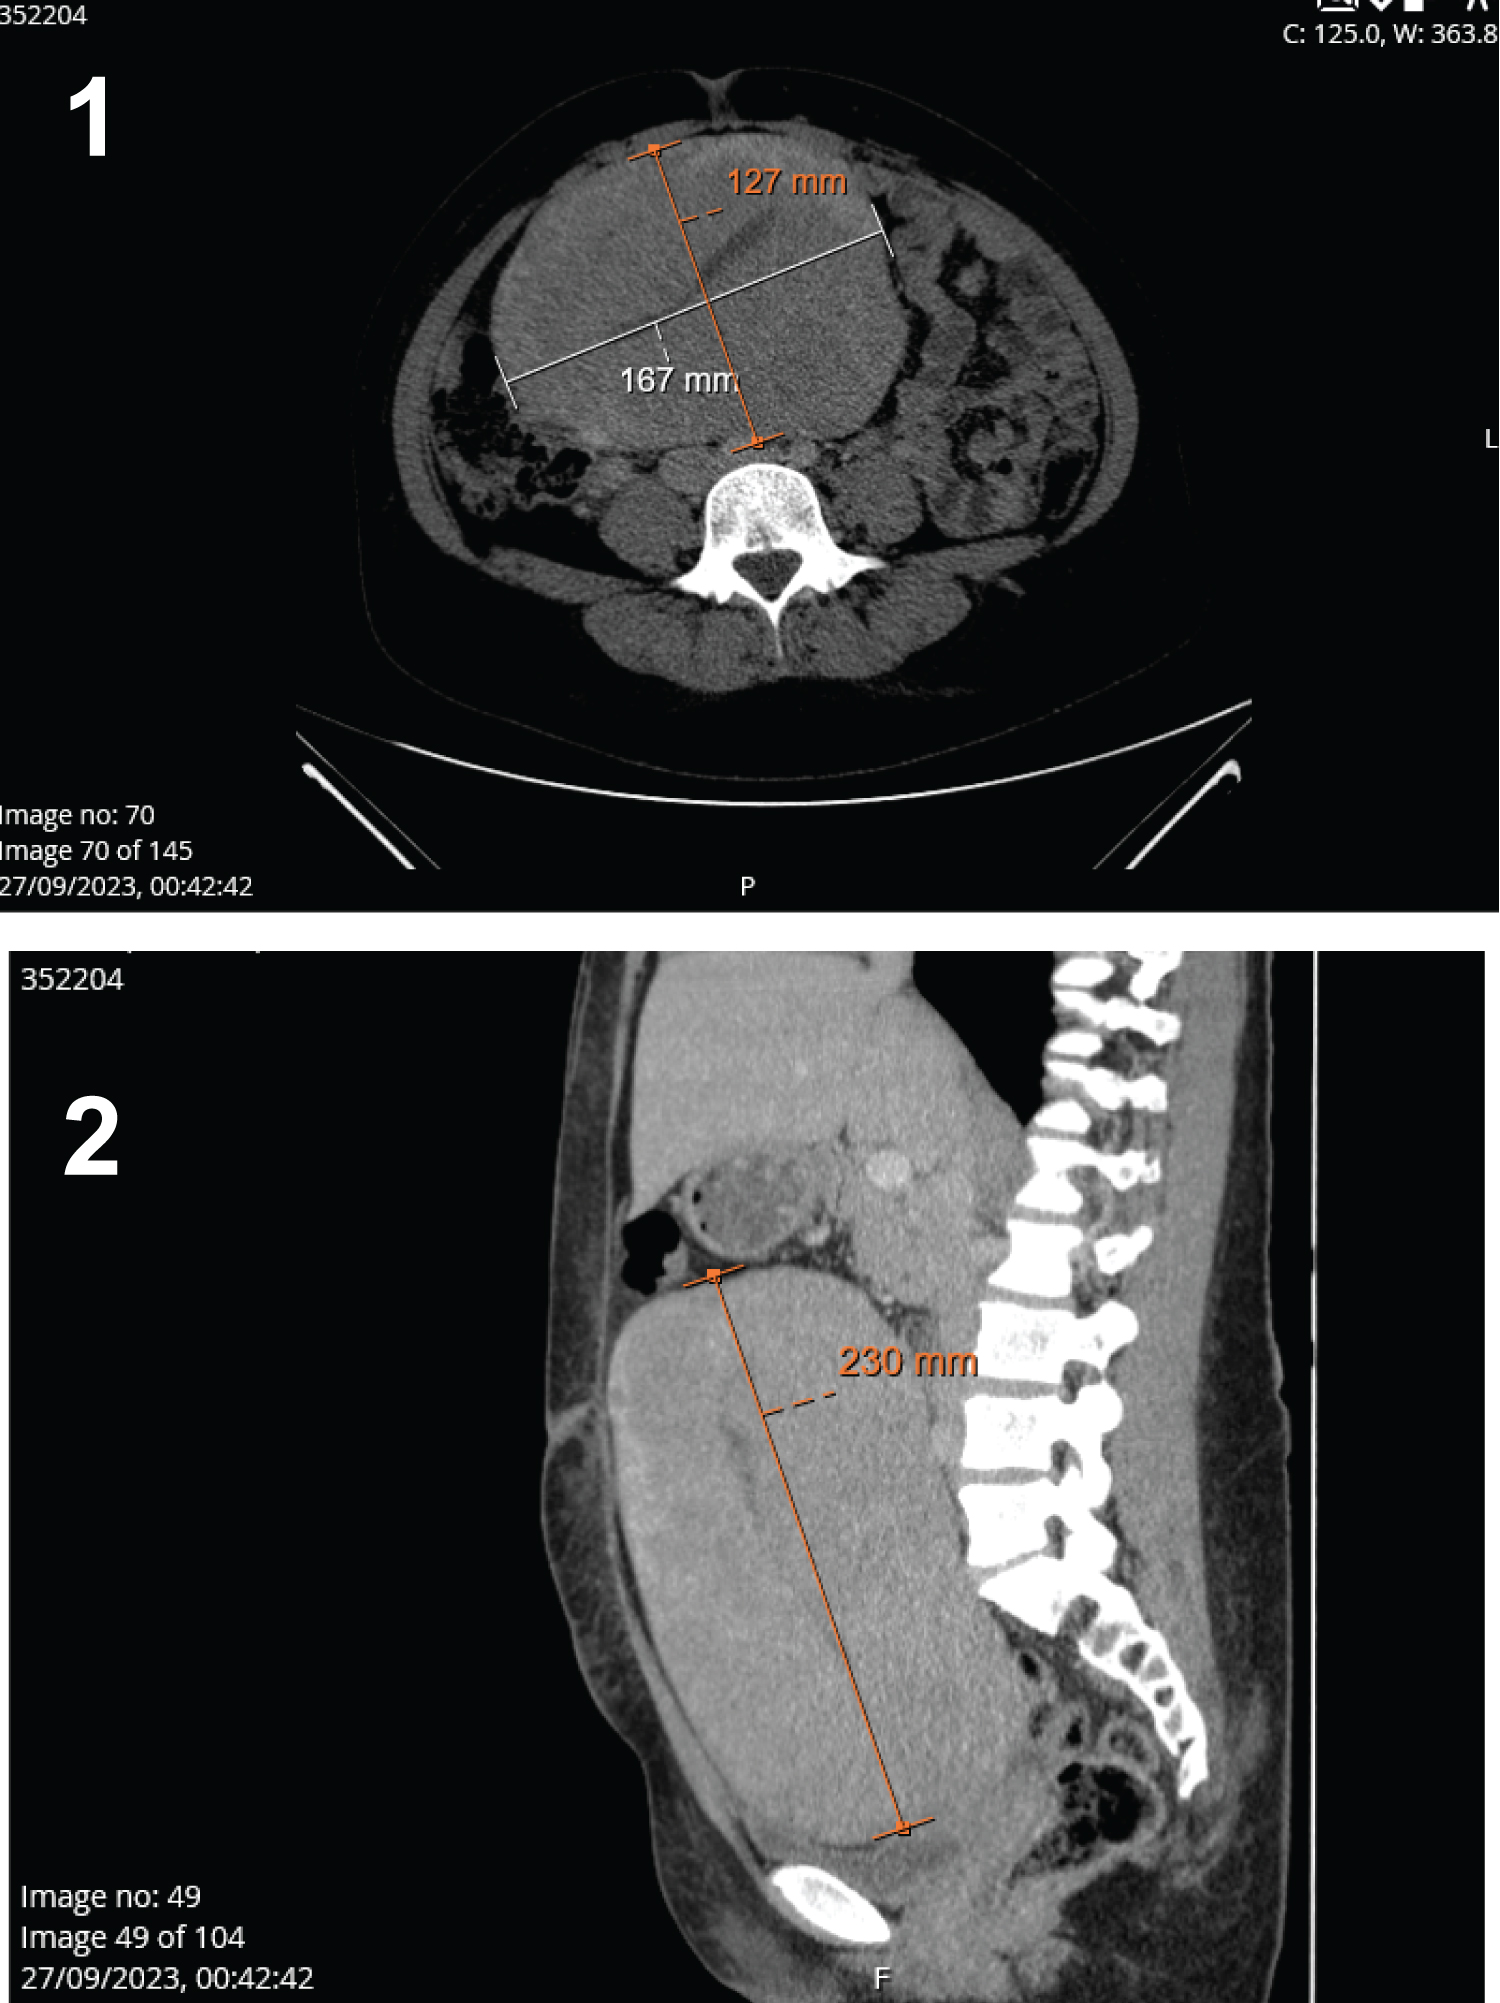

On the laboratory evaluation, she had serious anemia (Hemoglobin level of 4.6 g/dL), with no other major changes. To better characterize this mass, an abdominopelvic computed tomography (CT) was requested, which showed the existence of a large mass (with 17 * 28 cm of maximum diameters) with an apparent uterine origin - admitting possible leiomyomatous/sarcomatous lesion (Figure 1 and Figure 2). Lactic dehydrogenase and other tumor markers were all negative.

Figure 1 and 2: CT scan showing the enlarged uterus (with measures of its diameters).